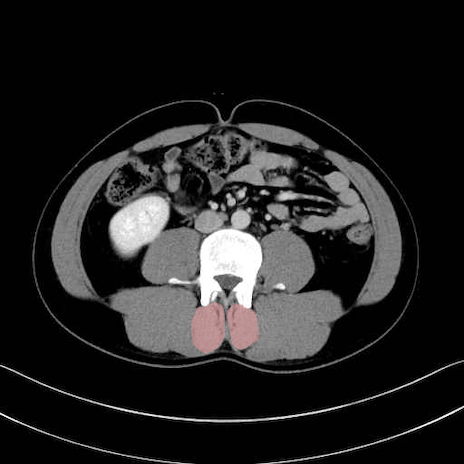

多裂筋 (Multifidus)